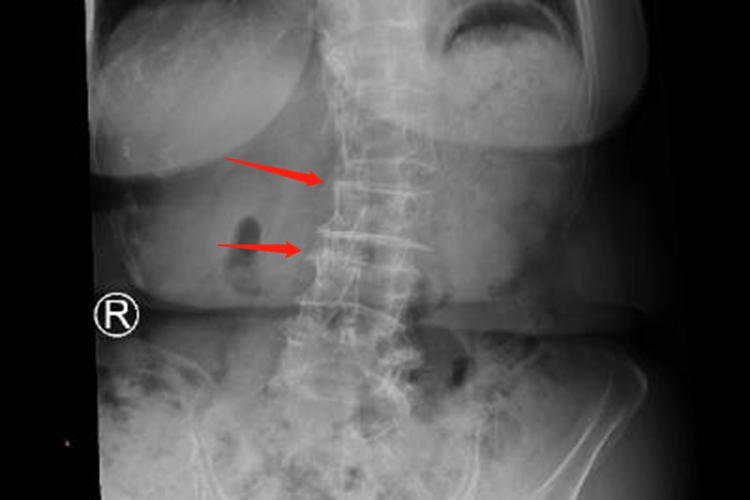

退行性脊柱侧弯可表现为腰椎的滑脱或侧方移位、腰部疼痛等症状,与脊柱椎间盘及椎间关节的不对称退行性改变有关,可行手术治疗。

退行性脊柱侧弯从退变开始就伴随着腰痛及椎间盘突出的症状,多数患者表现为腰椎的滑脱或侧方移位,患者进行影像学检查时可见脊柱侧弯,压迫神经时可有腰部疼痛,下肢有麻木胀痛症状,站立时间久时会有腰痛症状。